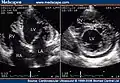

Trabeculation of the ventricles is normal, as are prominent, discrete muscular bundles greater than 2mm. In non-compaction there are excessively prominent trabeculations. Echocardiography is the reference standard for diagnosing NCC, although it can be well defined by computer tomography scan, positron emission tomography and magnetic resonance imaging.[13] Chin, et al., described echocardiographic method to distinguish non-compaction from normal trabeculation. They described a ratio of the distance from the trough and peak, of the trabeculations, to the epicardial surface.[14] Non-compaction is diagnosed when the trabeculations are more than twice the thickness of the underlying ventricular wall.

- Transthoracic two-dimensional echocardiogram in apical four chamber and parasternal short axis at the level of both ventricles demonstrate dilatation, deep trabeculae and intertrabecular recesses in the inferior, lateral, anterior walls, middle and apical portions of the septum and apex of the left ventricle.